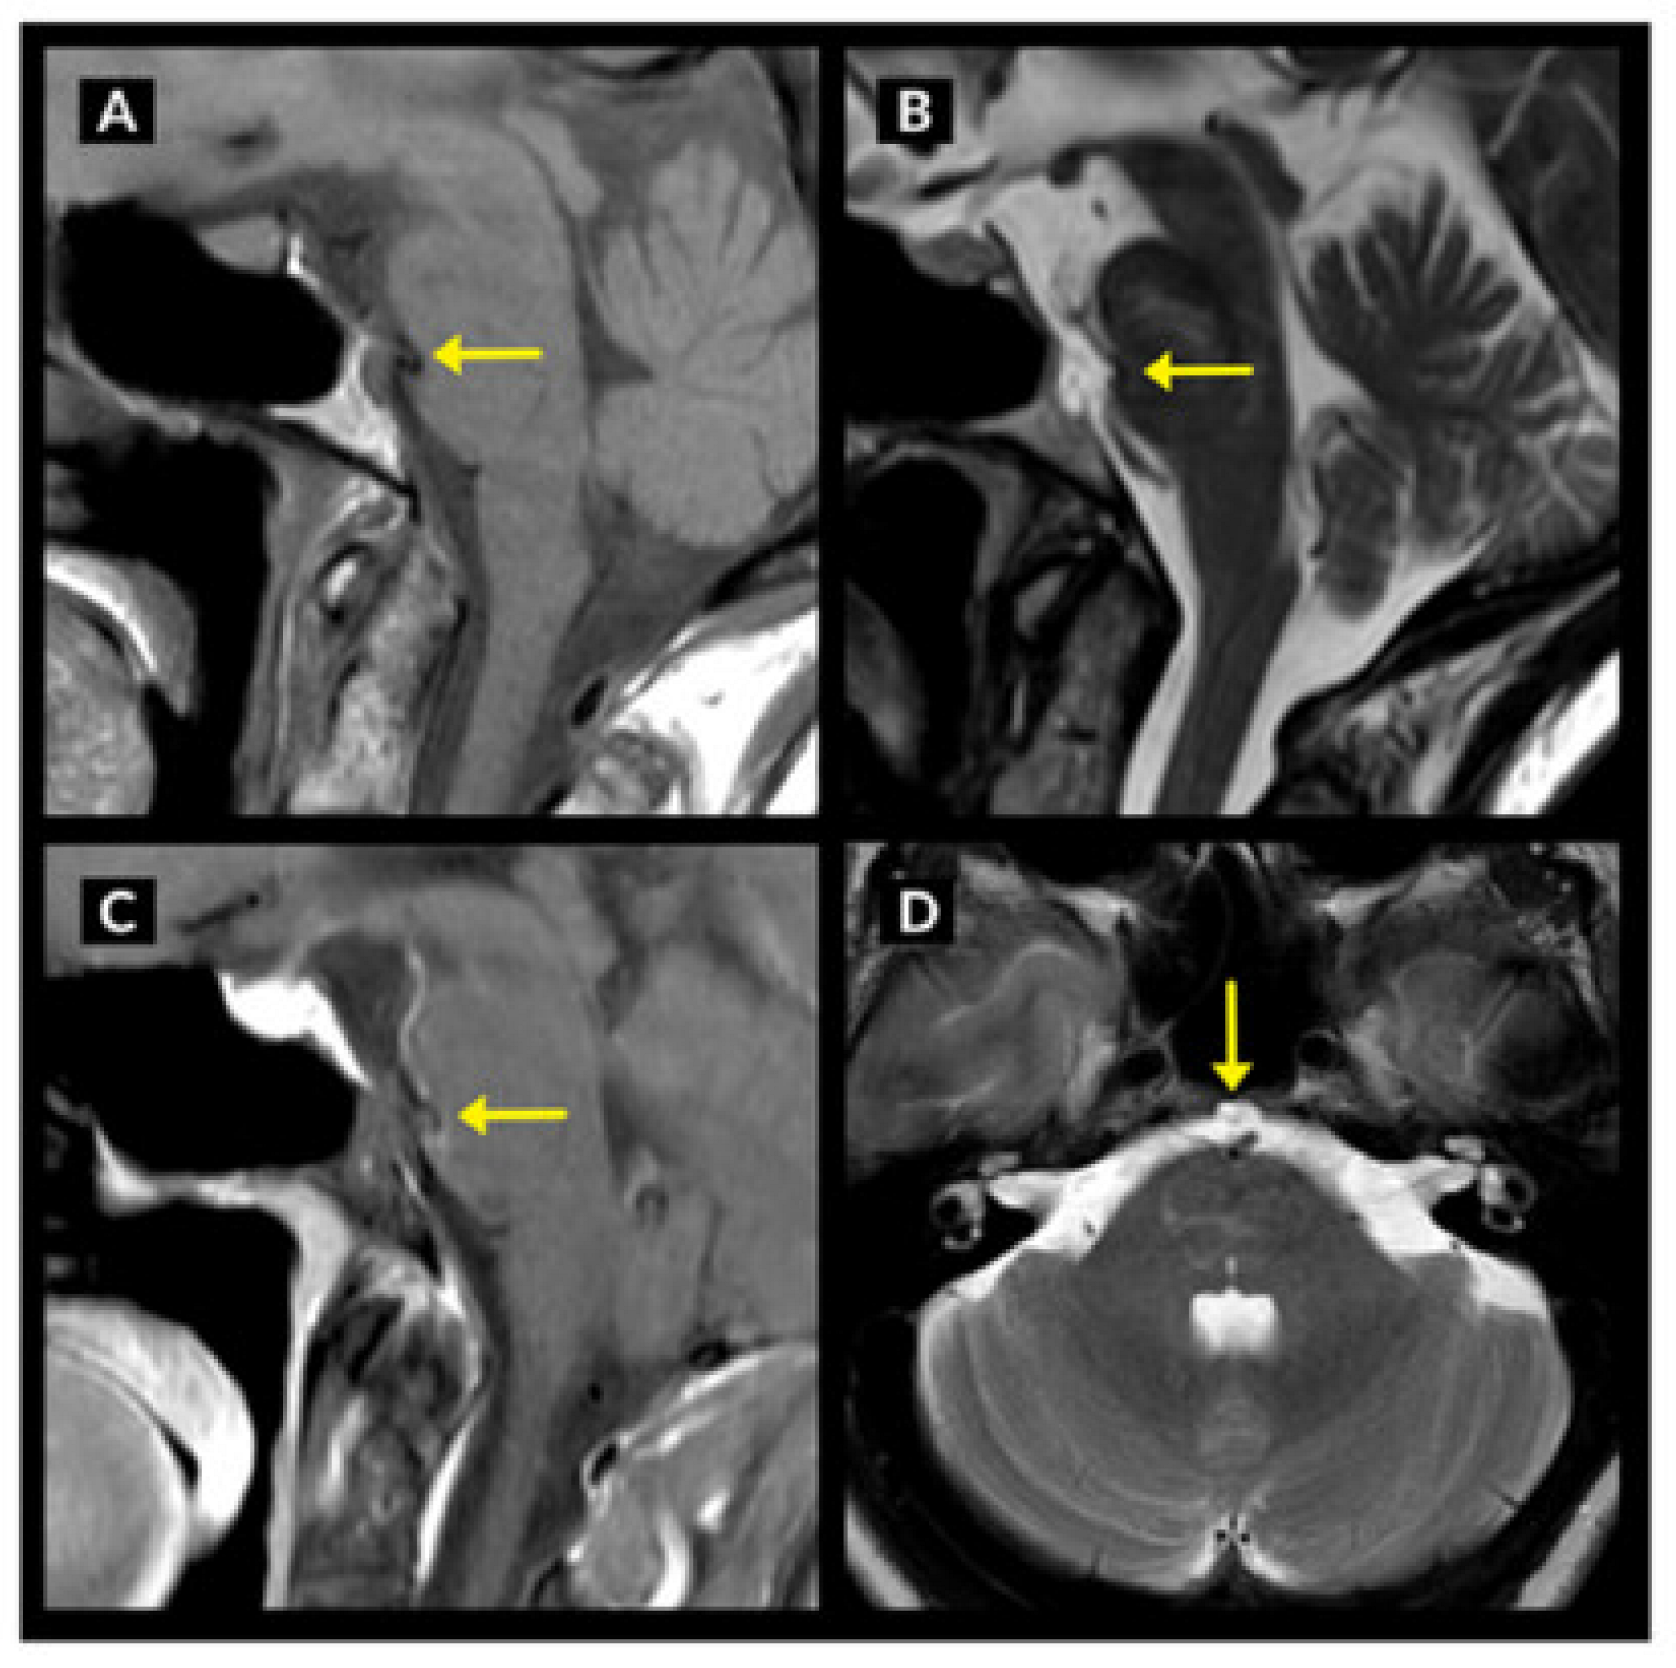

4.3.1. Imaging